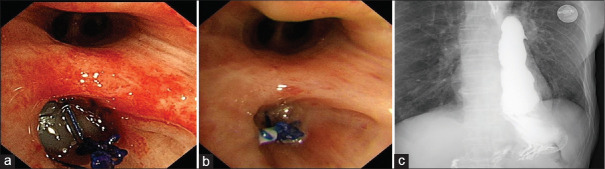

胃支气管瘘(GBF)是食管切除术后罕见但严重的并发症,具有很高的发病率和死亡率。硅胶塞的使用已被证明在其他情况下有效关闭支气管瘘,但其在GBF中的应用尚未被广泛描述。在本文中,我们报告了在支气管镜指导下使用自制硅胶塞成功关闭GBF的患者,该患者有食管癌食管切除术的历史。这种方法为治疗难治性GBF提供了一种安全、微创的替代方法。

Gastrobronchial fistula (GBF) is a rare but serious complication following esophagectomy, associated with high morbidity and mortality. The use of silicone plugs has proven effective in closing bronchial fistulas in other contexts, but its application in GBF has not been widely described. In this article, we report the successful closure of a GBF using a self-made silicone plug under bronchoscopic guidance in a patient with a history of esophagectomy for esophageal cancer. This approach offers a safe, minimally invasive alternative for managing refractory GBF.